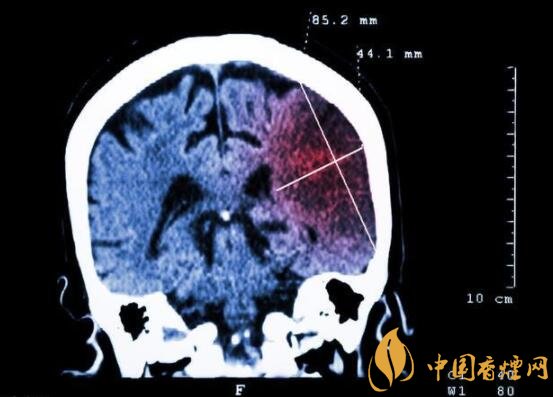

一般而言,急性腦梗塞與長期吸煙有非常密切的聯(lián)系。有長期煙齡遇到肢體活動不順,做頭顱核磁共振檢查往往查出一側(cè)大腦中動脈閉塞的可能性很高。由此可見,吸煙確實與中風存在一定聯(lián)系。

在這當中,吸煙者與不吸煙者做對比,發(fā)生中風時間可提前十年。按照每日吸煙1-20支,對比不吸煙者發(fā)生中風風險高出3.3倍;每日吸煙20支以上者,比不吸煙者高出5.6倍;30-40歲吸煙者,發(fā)生腦梗塞風險比不吸煙者高出5倍;50-60吸煙者,發(fā)生腦梗塞風險比不吸煙者高出3倍。由此可見,吸煙量越大,吸煙時間越長,發(fā)生中風的可能性越高,特別是多發(fā)生在中年